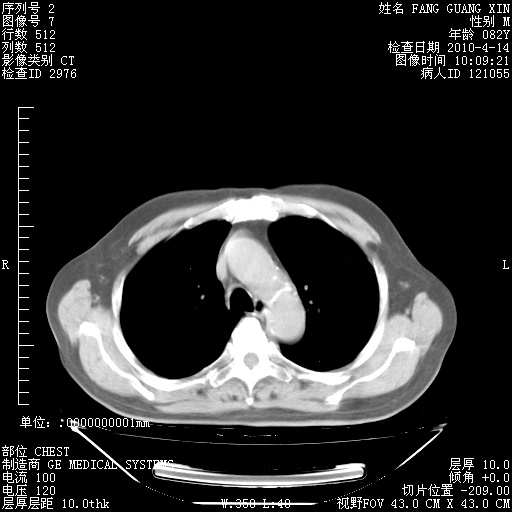

4月28日肺部CT——再次出现类似去年5月9日——透光度降低,(影像科认为)“间质性”改变。

4月28日肺部CT——再次出现类似去年5月9日——透光度降低,“间质性”改变。